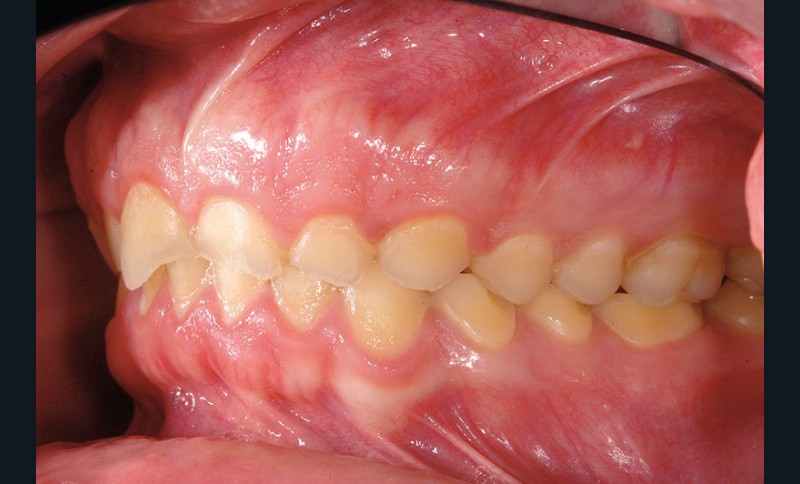

À l’examen clinique, les dents, principalement antérieures, présentent des pertes de substances importantes de classe V selon la classification ACE (Anterior Clinical Erosive Classification) de Vailati [1] (fig. 1 à 6).

Le parodonte marginal est de type 1 selon la classification de Maynard et Wilson [2]. On note également la présence d’une grande quantité de gencive attachée située apicalement par rapport aux lésions dentaires.